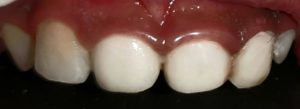

Treatment and Services